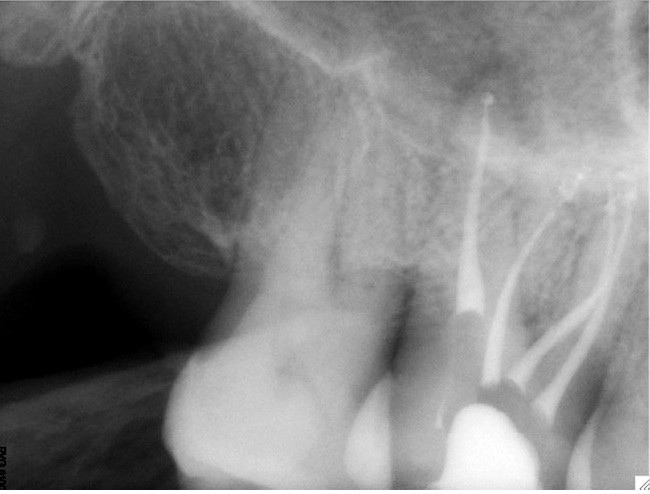

Endal, en 2011, montrait également, en utilisant le micro CT Scanner, l’insuffisance de nettoyage des isthmes inter-canalaires à nos techniques conventionnelles [19]. L’utilisation du laser Er:YAG devenait alors incontournable dans le nettoyage de ces isthmes et des zones non instrumentées (fig. 2 et 3).

Si l’étude de Peters [18] nous montre que l’instrumentation laisse 35 % du volume canalaire non instrumenté, Ricucci et Siqueira montrent que la préparation physico-chimique n’élimine que partiellement les tissus nécrotiques à l’entrée des canaux latéraux, des isthmes et des ramifications apicales, en laissant des tissus enflammés et infectés, en association avec des lésions apicales [29] (fig. 4 et 5).

Fig. 4 – Coupe d’une racine mésiale de molaire mandibulaire avec deux canaux traités. Coupe à 3 mm de l’apex, coloration Brown et Brenn, technique modifiée par Taylor. Ces images montrent un isthme étroit avec une infection bactérienne, ce qui prouve l’importance de désinfecter et d’inclure l’isthme dans les traitements conventionnels et dans les rétropréparations apicales en chirurgie endodontique.